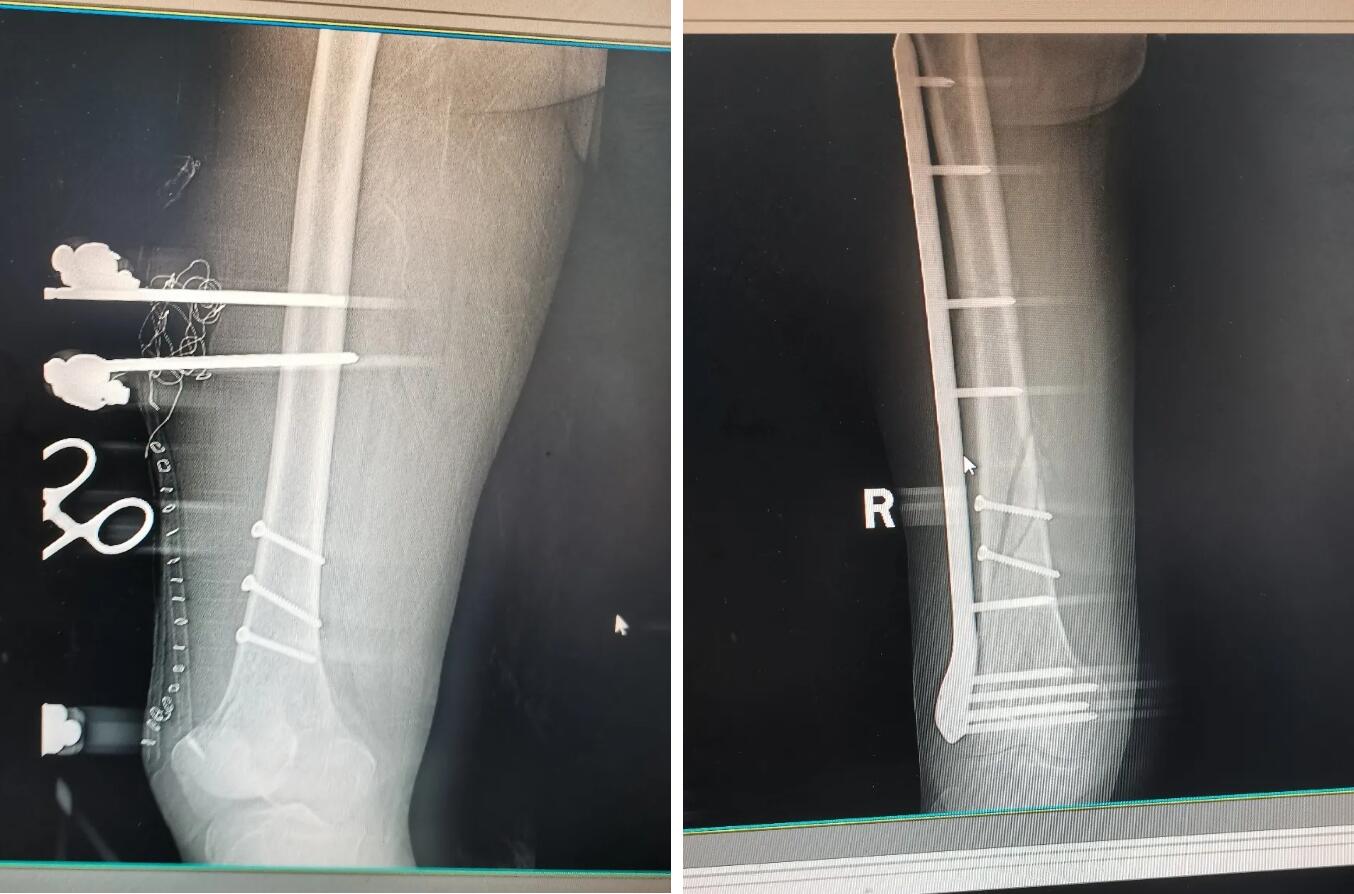

▲陈先生(右二)及家属(左一)给足踝医学科主任王永松(左二)、主刀医师郭真(右一)送锦旗

▼

足踝医学科主任王永松诊断为“右股骨开放性粉碎性骨折、右胫踝间棘骨折”,经过主刀医师郭真的精准手术,断骨被接回去了,破损的皮肤也移植成功了。陈先生恢复情况良好,已经能借助外力(拐杖)独立行走。